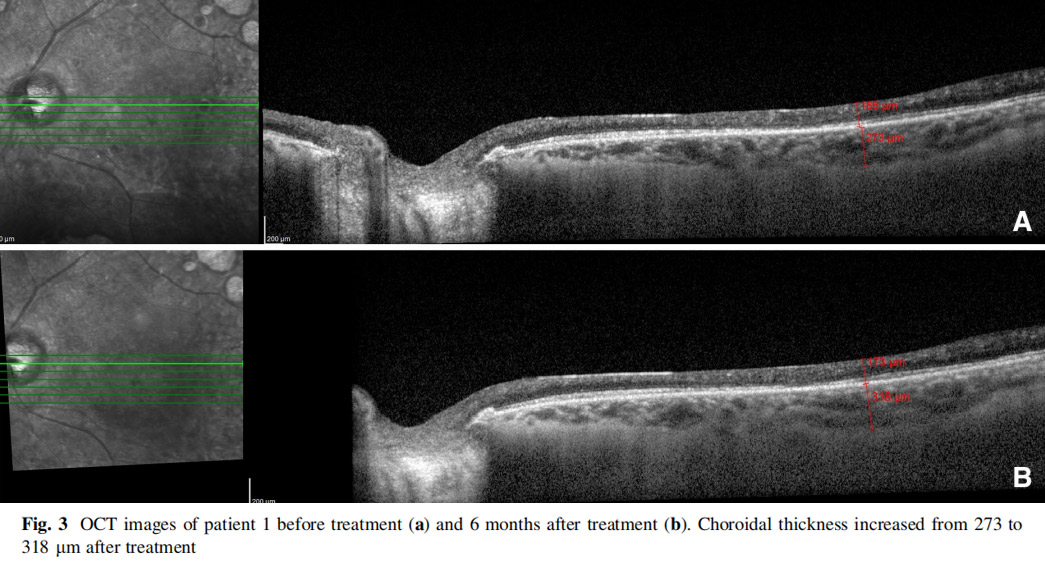

患者左眼接受AD-MSCs治療,6個月后視力提高至2米處數手指(CF)水平,視野中央島狀結構擴大,如圖1所示,左眼mfERG顯示改善(圖2),脈絡膜厚度從273μm增加至318μm(圖3),黃斑厚度和RNFL沒有變化。